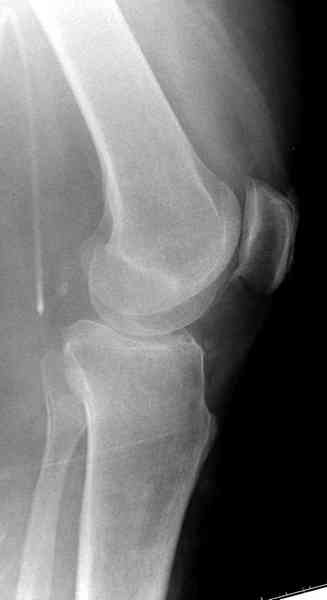

Из медиального окна можно приподнять латеральную

импрессию. Фиксация тремя параллельными шурупами в

эпифизарной части над импрессией. Создается крыша,

которая предупредит коллапс. На образовавшуюся полость - костная пластика из аутокости или синтетический заменитель. Мы применяем Osteoset в 4-5 мм диаметре таблеточки или иньекционную форму Prodens.